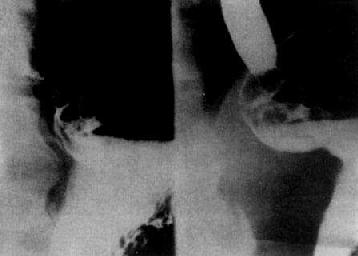

图4-2-17 胃窦癌(溃疡型)

胃窦部小弯侧腔内不规则龛影,

其周围 有不规则的环堤